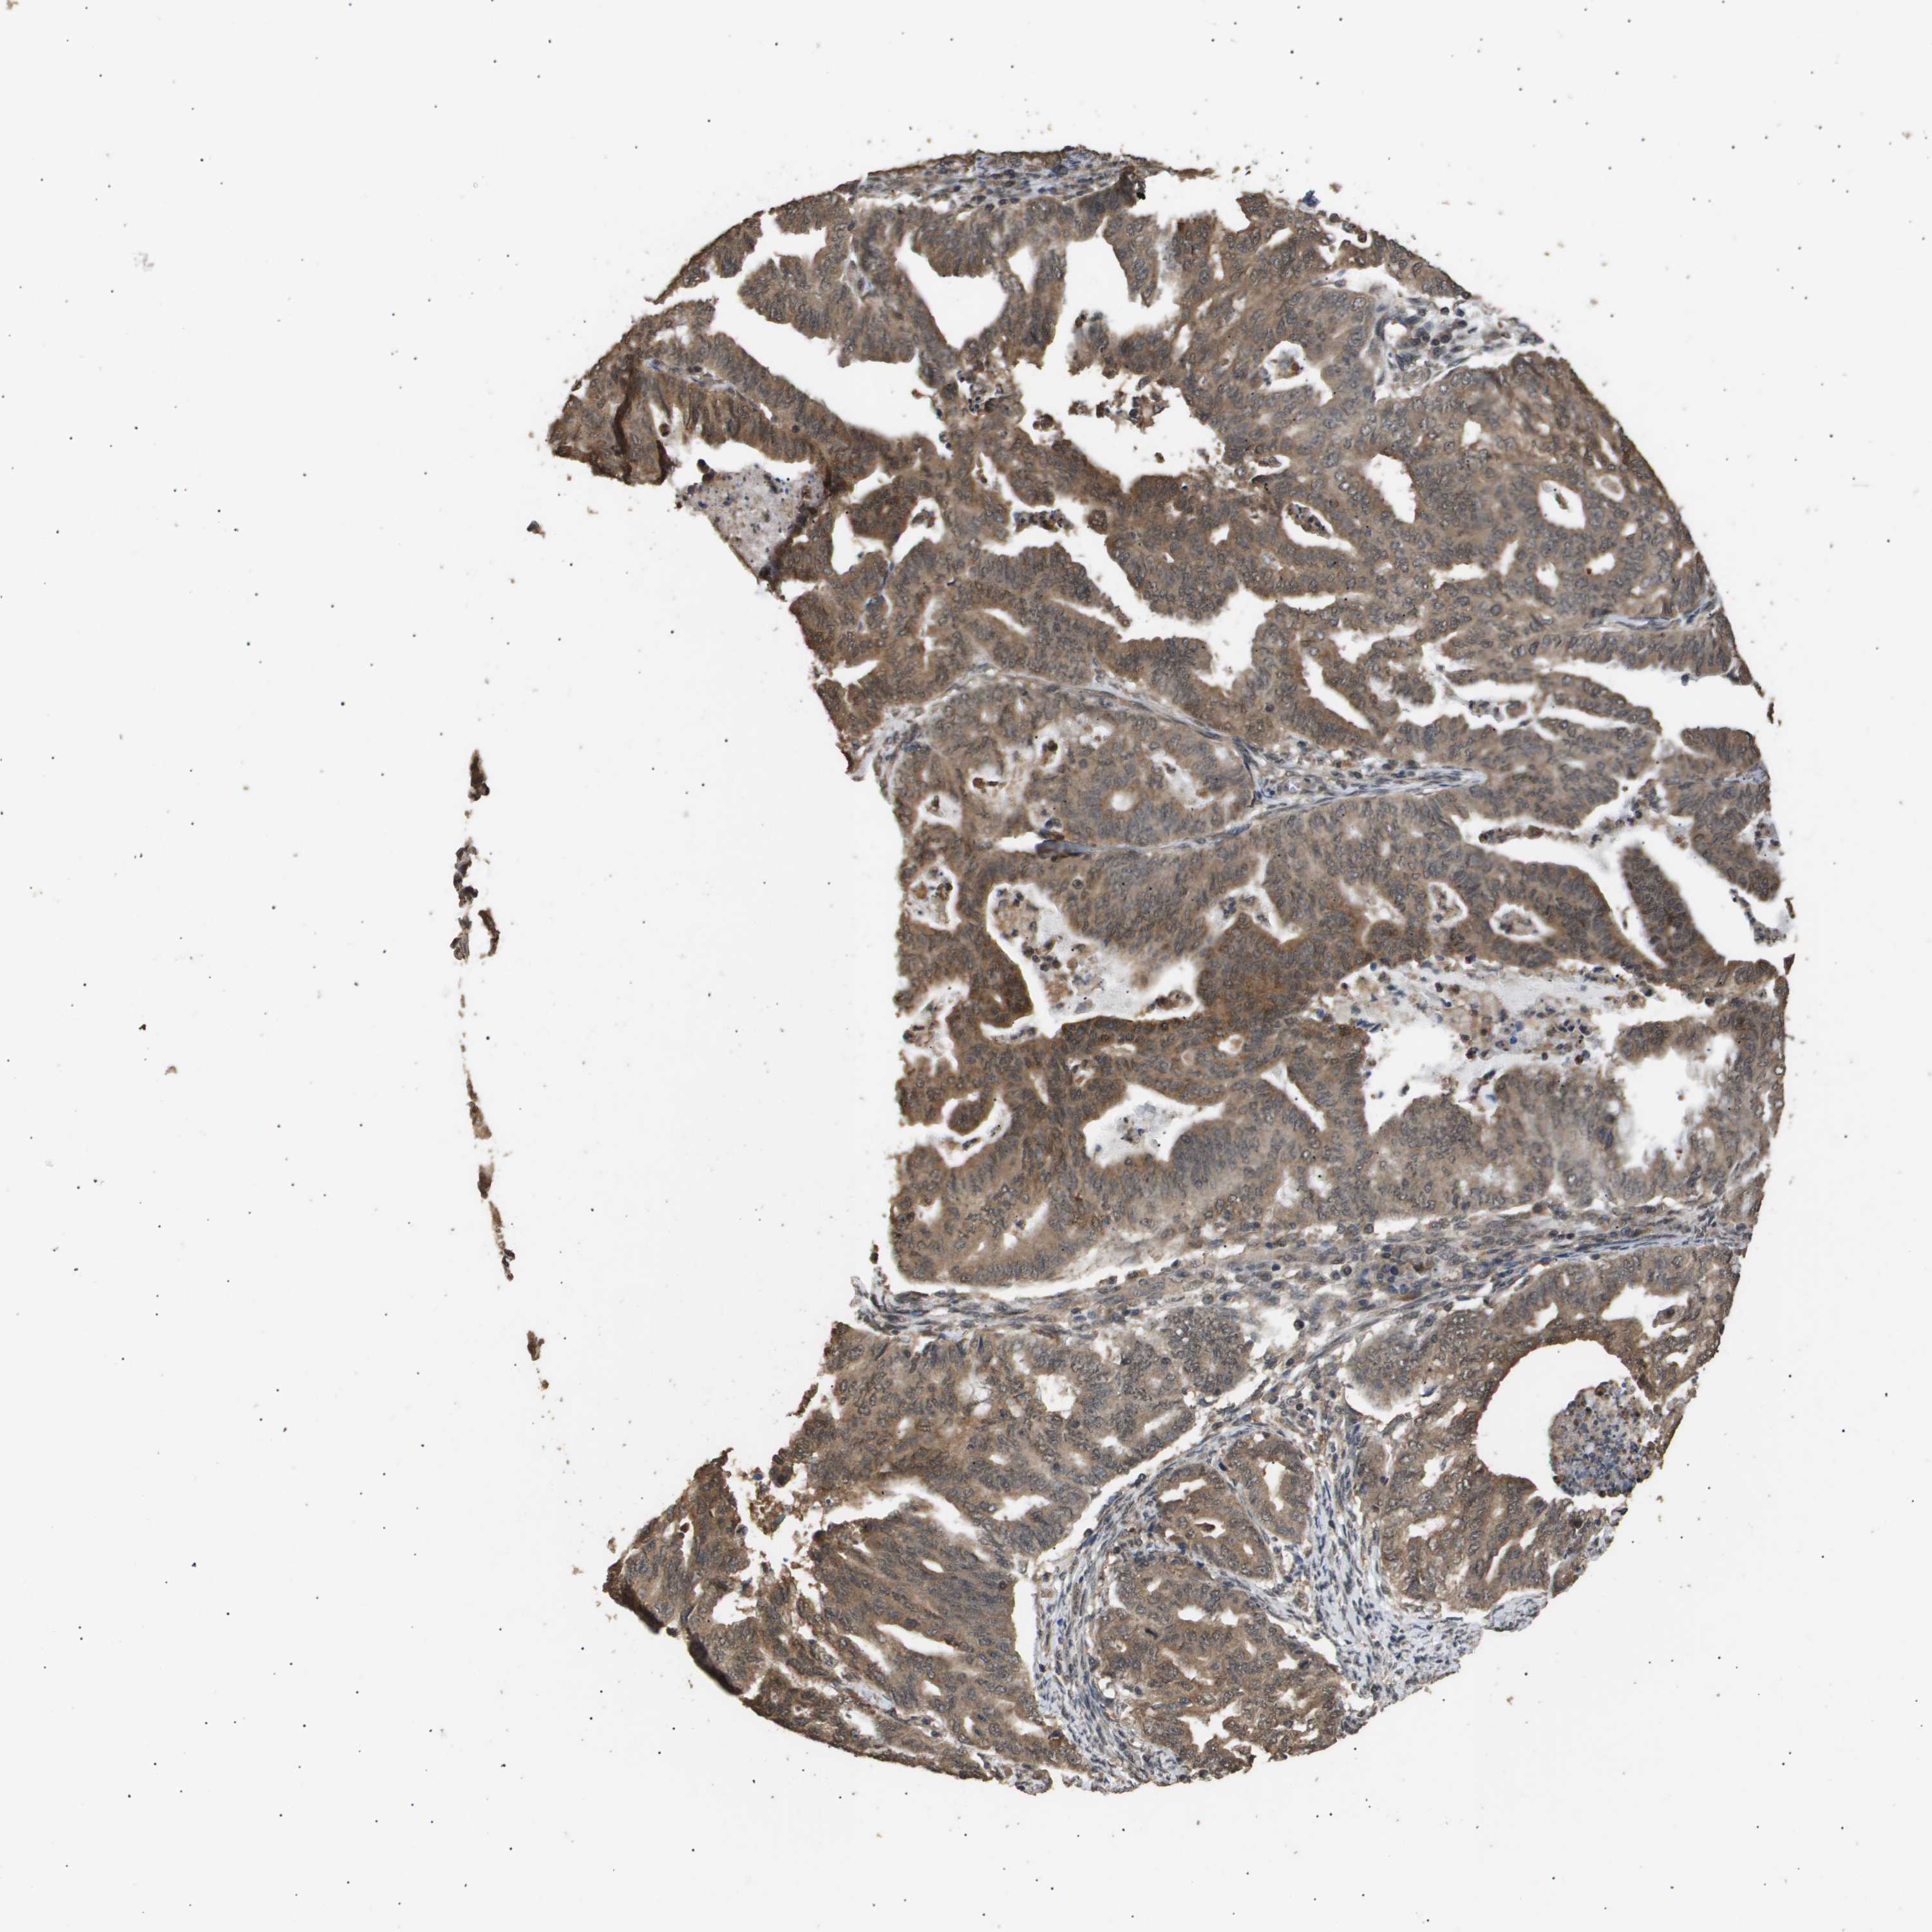

ENDOMETRIAL CANCER - Protein expressioni

A mouse-over function shows sample information and annotation data. Click on an image to view it in a full screen mode. Samples can be filtered based on level of antibody staining by selecting one or several of the following categories: high, medium, low and not detected. The assay and annotation is described here.

Note that samples used for immunohistochemistry by the Human Protein Atlas do not correspond to samples in the TCGA dataset.

Antibody stainingi

Antibody staining in the annotated cell types in the current human tissue is reported as not detected, low, medium, or high, based on conventional immunohistochemistry profiling in selected tissues. This score is based on the combination of the staining intensity and fraction of stained cells.

Each image is clickable and will lead to virtual microscopy that enables deeper exploration of all samples and also displays staining intensity scores, fraction scores and subcellular localization as well as patient and tissue information for each sample.

Antibody CAB016136

Antibody CAB017773

Staining

High

Medium

Low

Not detected

Intensity

Strong

Moderate

Weak

Negative

Quantity

>75%

75%-25%

<25%

None

Location

Nuclear

Cytoplasmic/membranous

Cytoplasmic/membranous,nuclear

Adenocarcinoma, NOS